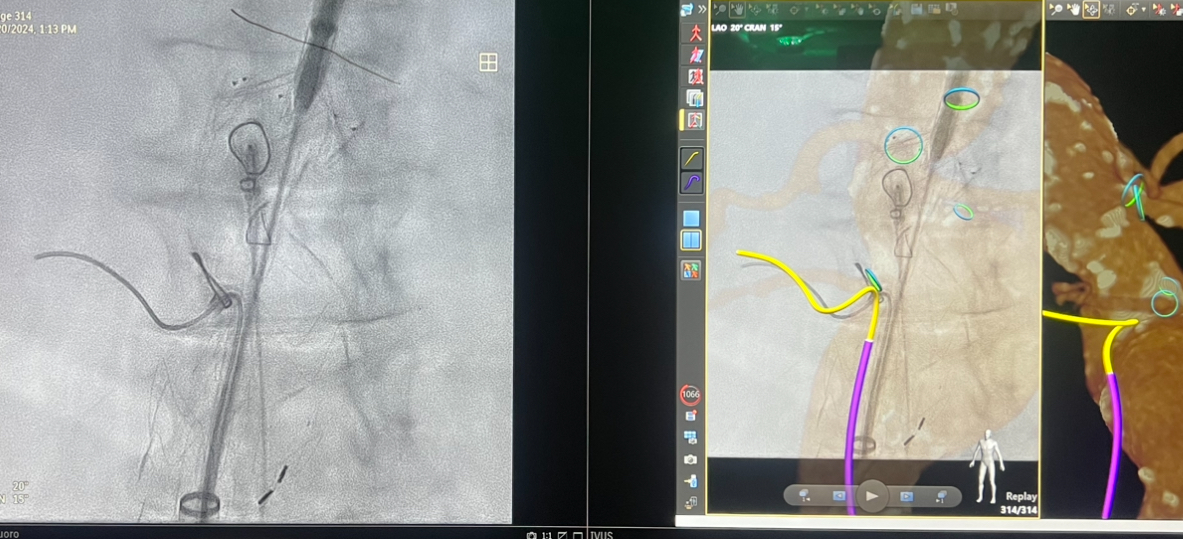

This new technology generates 3D, real-time, color visualizations providing multiple views of the anatomy allowing the surgeon to navigate more accurately through the patient’s body. This advanced imagery improves upon the 2D, grayscale images previously available using x-ray alone and will initially be used during endovascular aortic procedures.